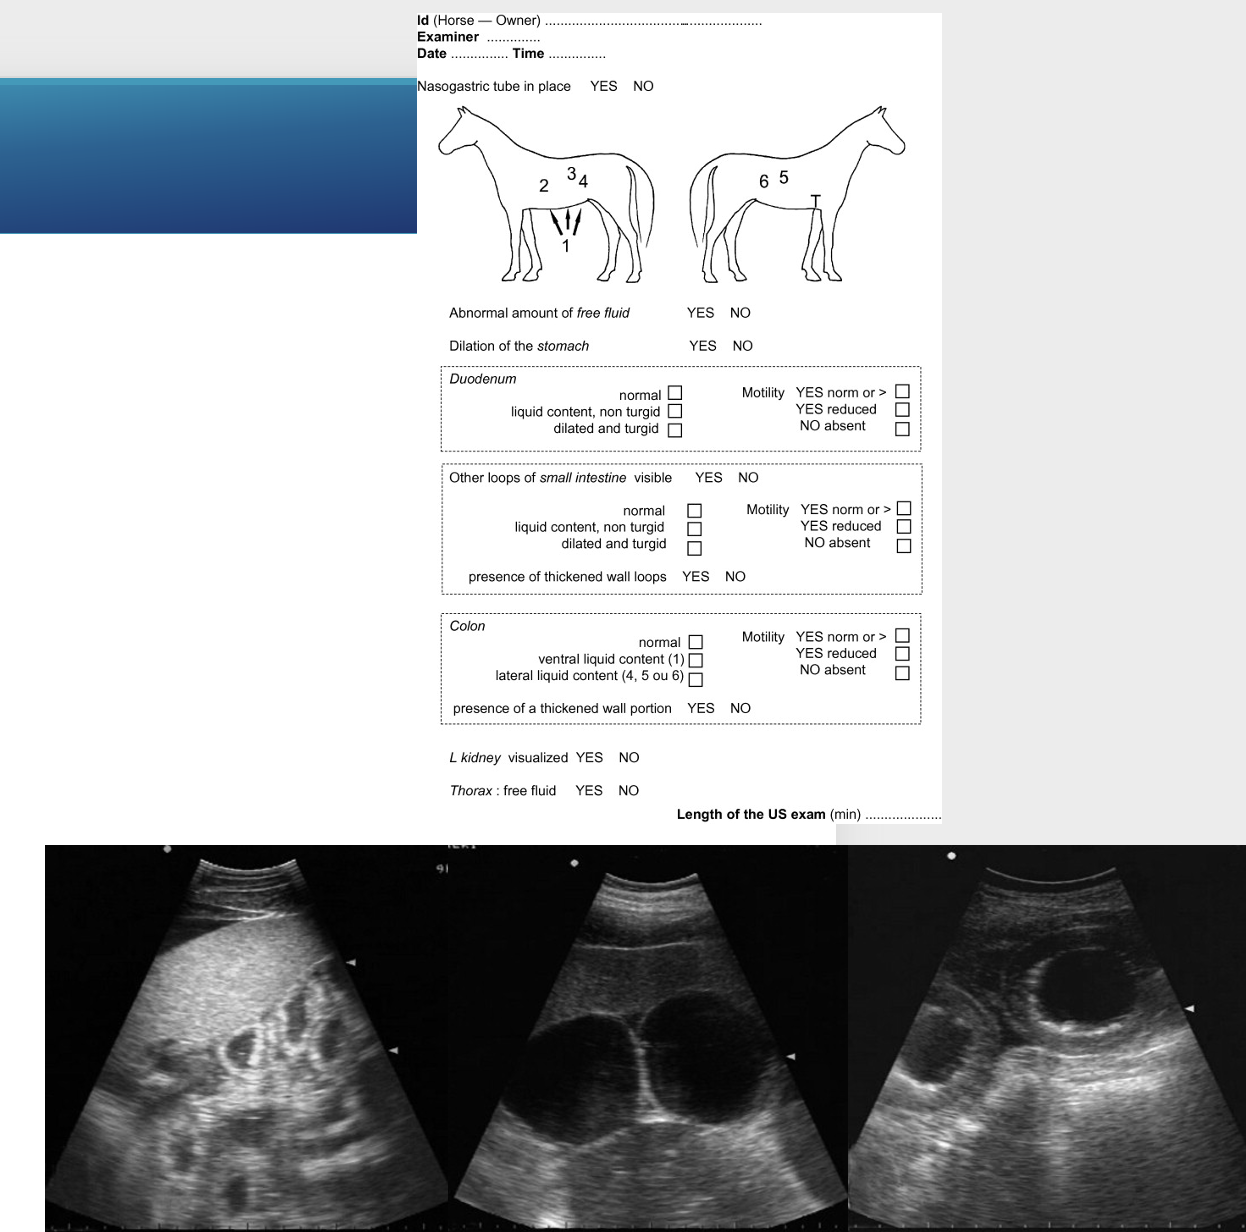

16

Q

What is FLASH

A

Fast localised abdominal sonography of horses

Allows for assessment of abdominal & thoracic free fluid & assessment of small intestinal loops

7 point scan

Has worksheet to help you look for the right things

Dilated turgid small intestinal loops 80% sensitive & 96% specific for SI obstruction so you know it’s surgical case